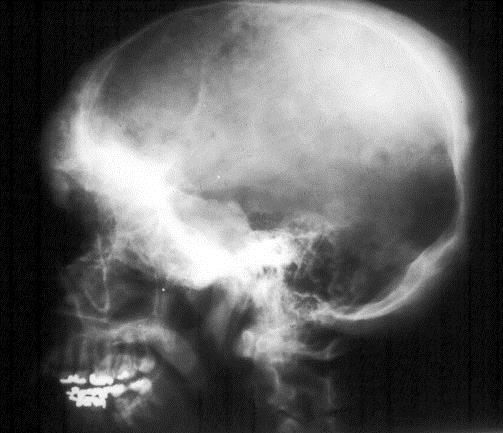

Craniofacial bones are affected in 10-25%. In the skull, the base is most often involved with dense sclerosis (Figure 3).

Figure 3: FD skull. Note diffuse sclerosis of the bones at the base.